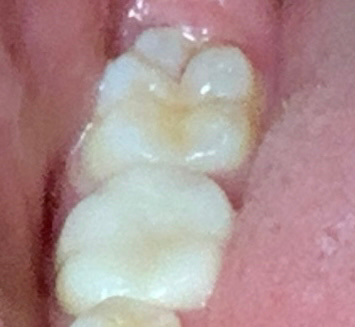

까맣게 보이기는 하는데 다른 검은게 끼인것인지, 충치인지 확실하지는 않네요.어쩌면 충치가 맞는데 너무 작거나, 멈춘 충치라서 아직 치료시기가 아니라고 생각하셨을 수도 있고요.

충치를 긁어봤을때 긁히지않는다면 진행이 멈춘것으로 보고 치료를 하지 않는경우도 있습니다

치아에 생기는 충치중에는 진행.중인 충.치와 정지된 충치가 있습니다.

진행되는 충치는 갈색의 연한성.질을 띠.고 있는데 치료를 안하면 크게 진행이 되기 때문에 빠르게 치료를 하는.것이 좋.습니다.

정지된 충치는 석회화가 되어 있.어서 진.행이 되지 않기 때문에 크게 문제를 발생하지 않지만 심미적으로 신경.이 쓰인.다면 치료를 할수 있습니다.

정확한건 직접봐야 알겟지만, 사진상으로 보면 범위도 넓지 않고 정지된 충치라서 지켜보자고 하신것같습니다.

정지우식인 경우 충치치료를 하지 않고 보류할수 있습니다..더 이상 진행이 되지 않도록 치아관리를 잘 해야합니다..치료받는 시기를 놓치게 될수 있습니다.